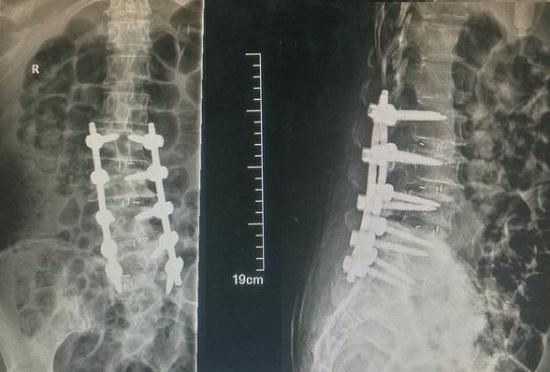

当腰椎发生严重退变并诱发显著症状时,往往需要通过外科手术的方式进行治疗。腰椎融合术是应用最为广泛的一种脊柱手术,这类手术的原理大概是这样的:采用固定装置将发生退变的腰椎节段与相邻节段固定在一起,并通过骨移植或融合器的方式填充椎体间隙,让退变的腰椎节段产生永久性连接。显而易见,腰椎融合术不仅会有一定的&白桦茸#9442570599;、手术风险,还会导致被融合节段的减震功能和运动功能丧失,使相邻节段加速退变。尤其让人难以接受的是,没有�人可以确保腰椎融合术就一定能够令人满地解决疼痛、神经压迫等症状。因此,在决定实施腰椎融合术前,首先要进行至少6个月的保守治疗,在保守治疗无效的情况下,才会根据患者情况考虑是否实施腰椎融合手术。腰椎融合术的适应证如下所列。

腰椎融合原理示意图

针对腰椎侧凸和腰椎退变实施的腰椎融合术